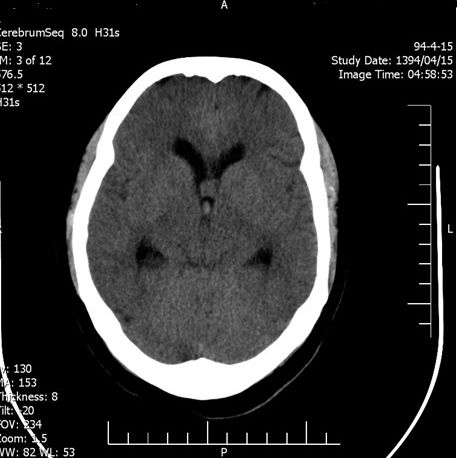

Background: Cavernous hemangiomas are common benign vascular malformations. Their existence in the intraventricular region is very rare. Case Reports: A 43-year old woman with an occipital headache was admitted to the emergency ward. Brain computed tomography scan showed mild hydrocephalus and multiple intraventricular isodense lesions. Imaging findings, especially of Gradient Resonance Echo imaging, were in favor of multiple intraventricular cavernous malformations. Conclusion: This is a rare presentation of multiple cavernous malformation as occipital headache without needing surgical intervention in this phase. Coexistence of periventricular plaques like Radiologically isolated syndrome of Multiple sclerosis is another unique aspect in this report. [GMJ.2017;6(1):61-65]